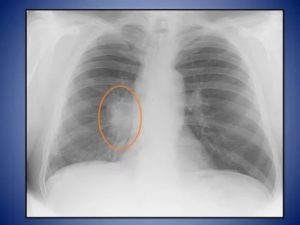

После проведения обзорной рентгенографии грудной полости в двух проекциях врач-рентгенолог ставит заключение: «Корни легких уплотнены и малоструктурны».

Нарушение структуры корня легкого, то есть невозможность отличить сосуд от бронха, появление затемнения на корне, обычно встречается при первичном туберкулезе, онкологических процессах.

На рентгенограмме при обширном туберкулезе или центральном раке легкого вместо корня может визуализироваться тень различных контуров, представляющая собой очаг (до 10 мм диаметром) или инфильтрат (более 10 мм).

Данный симптом может также сочетаться с уплотнением, что обычно бывает при отложении солей кальция или обызвествлении (петрификации). Обызвествление является признаком хронического, долго протекающего процесса.